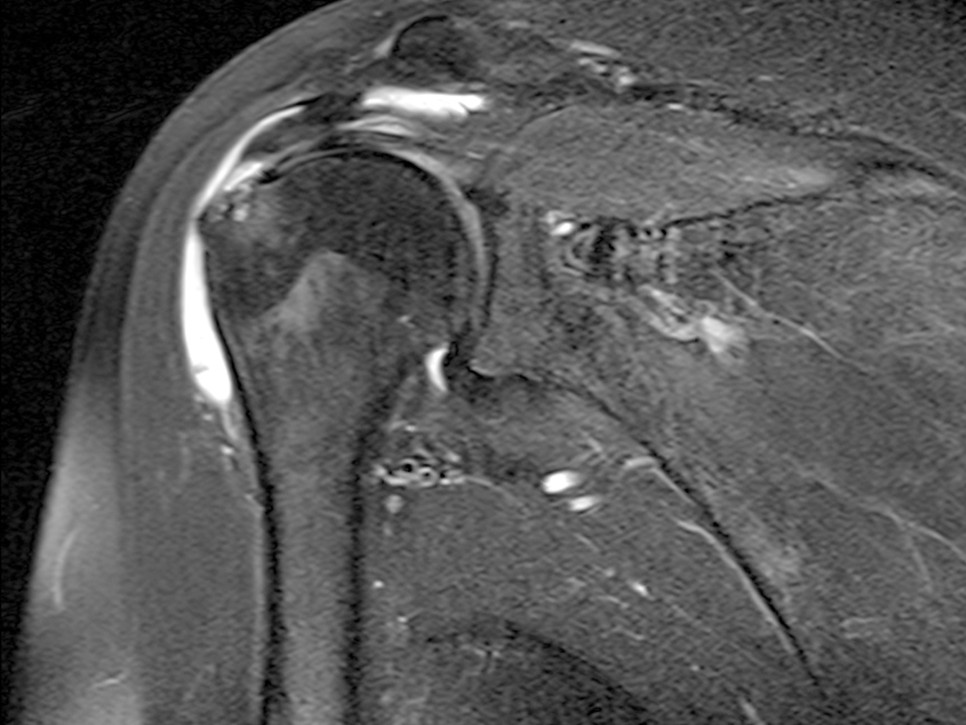

- 진단은 x선과 같은 단순 방사선 검사로는 어렵고 정확한 진단 및 감별 진단을 위해 MRI 촬영이 필요한 경우가 많습니다.

- 유사한 왼쪽 어깨 통증을 유발하는 질환인 어깨 둘레 근개 파열이 있습니다. 증상만으로는 구별할 수 없지만 어깨 회전근개 파열은 특정 범위의 동작만으로 통증이 유발된다면 오십견은 다양한 각도에서 통증이나 운동 제한이 발생합니다.